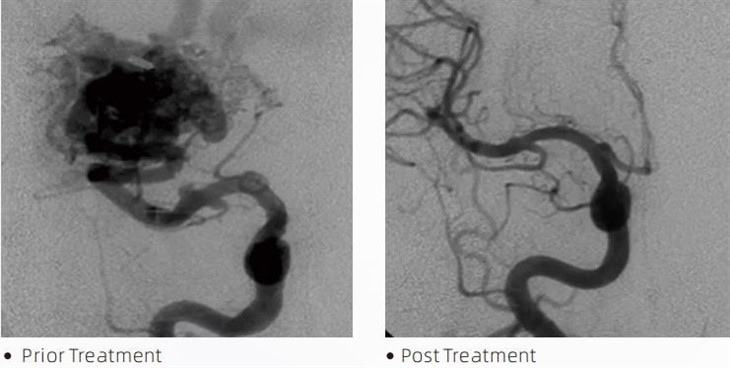

لاواٹی ایمایمبولک گلو ایک طبی آلہ ہے جو انٹروینشنل نیوروراڈیولوجسٹ کے ذریعہ کم سے کم ناگوار طریقہ کار کے دوران دماغی اینوریزم، آرٹیریووینس خرابی اور ٹیومر جیسے حالات کے علاج کے لیے استعمال کیا جاتا ہے۔ لاوا ایمبولک گلو طبی پیشہ ور افراد اور مریضوں کو حفاظت، استعمال میں آسانی اور تاثیر کے لحاظ سے ایک جیسے متعدد فوائد فراہم کرتا ہے۔ لاوا خون کی نالیوں کو جلدی اور مؤثر طریقے سے سیل کرنے کے قابل ہے۔ اس عمل میں گلو کو براہ راست ہدف والے برتن میں داخل کرنا شامل ہے، جہاں یہ پولیمرائز اور سخت ہو کر کاسٹ نما ماس میں تبدیل ہو جاتا ہے جو اینوریزم یا خرابی کو بھرتا ہے۔ پھر یہ مؤثر طریقے سے زخم میں خون کے بہاؤ کو کاٹتا ہے، اسے پھٹنے سے روکتا ہے اور مستقل نقصان یا فالج کے خطرے کو کم کرتا ہے۔ لاوا میں Lava-12، Lava-18 اور Lava-34 شامل ہیں۔ ہر فارمولیشن کو مخصوص طبی ضروریات کو پورا کرنے کے لیے ڈیزائن کیا گیا ہے۔ Lava-18 عام استعمال کے لیے معیاری فارمولیشن ہے۔ لاوا-34 تیز بہاؤ والے برتنوں کے لیے ہائی وسکوسیٹی گلو ہے۔ جبکہ لاوا-12 میں کم وسکوسیٹی ہے اور یہ زیادہ بہاؤ کے قابل ہے، جس سے ڈسٹل مائیکرو ویسلز کی اجازت ہوتی ہے۔ ان اختیارات کے ساتھ، انٹروینشنل نیورراڈیولوجسٹ بہترین نتائج کو یقینی بنانے کے لیے مناسب لاوا فارمولیشنز کا انتخاب کر سکتے ہیں۔ لاوا کی سب سے نمایاں خصوصیات میں سے ایک اس کی غیر چپکنے والی خصوصیات ہیں۔ یہ مادہ خاص طور پر اس وقت تک مستحکم رہنے کے لیے تیار کیا گیا ہے جب تک کہ یہ ہدف شدہ علاقے تک نہ پہنچ جائے۔ اس خصوصیت کا مطلب یہ ہے کہ لاوا ایمبولک گلو کو شریان کے اندر درست طریقے سے رکھا جا سکتا ہے اور ارد گرد کے بافتوں سے چپکے یا جڑے بغیر وہاں رہ سکتا ہے۔